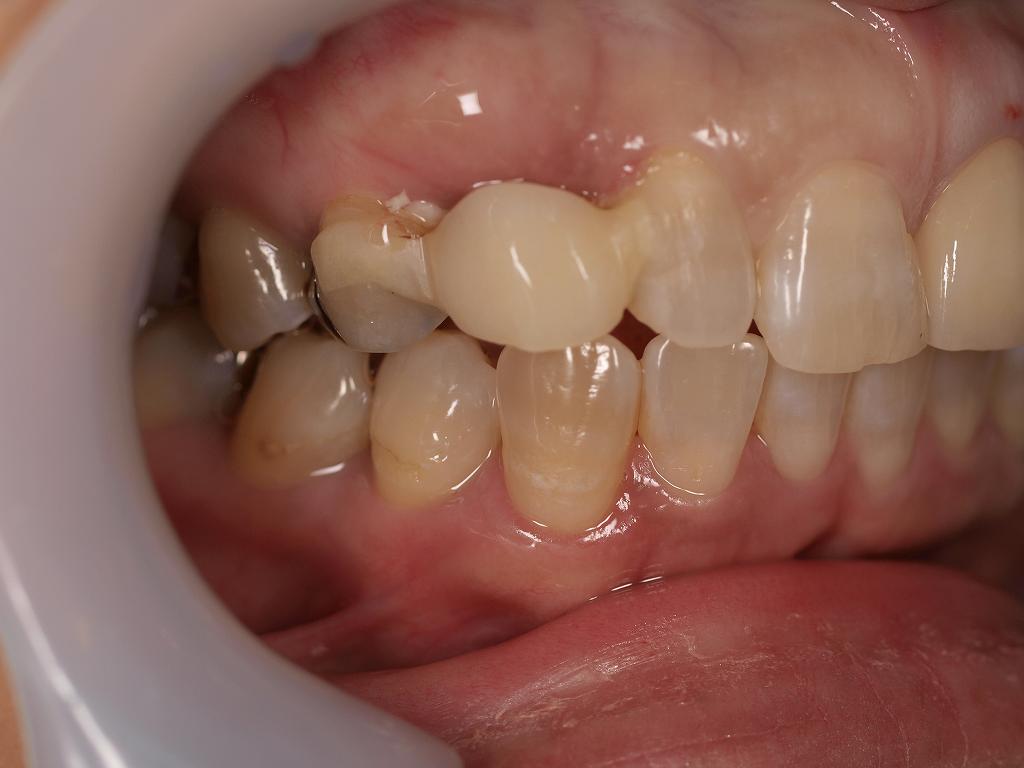

術前の口腔内

乳歯をそのまま使ってきていました

骨内に歯がほとんど埋まっていなく後継永久歯もありません